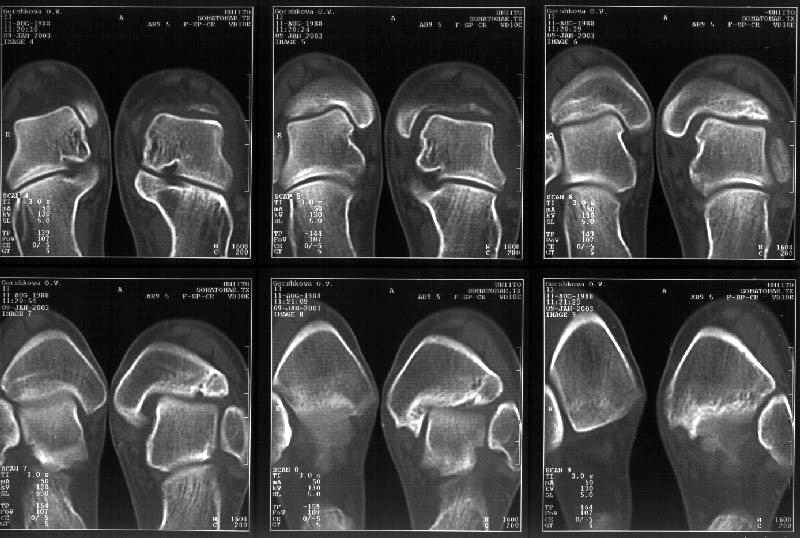

Сегодня пациентке сделали сравнительную КТ. А ксиальные и Фронтальные срезы приложены. Ваше мнение?

Фронтальные

Аксиальные

На КТ я попытался изобразить скромными своими способностями (А)- место перелома, (С)- нормальный суставной зазор меж тараном и тремя его маллеолами. (В)- образовавшийся в результате перелома широкий раза в три зазор, позволяющий, по-моему, сублюксацию тарана при ходьбе. В свете данных КТ, критически важных, я бы предложил вертикальную остеотомию места перелома

задне-внутренним подходом и фиксацию мед. маллеола прижатым к тарану с помощью тонкого compression screw. После этого гипсовый сапожок и немедленное расхаживание ноги.